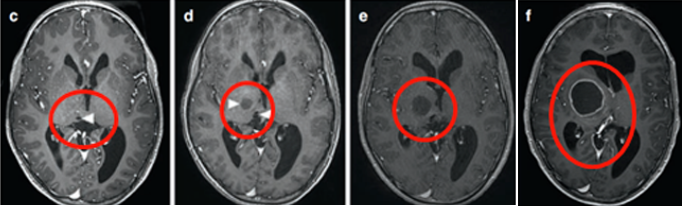

在13岁时,小率接受了神经导航和超声引导下的活检,证实肿瘤为WHO I级毛细胞星形细胞瘤。为了治疗多发囊肿,鲁特卡教授在超声引导下将Ommaya导管和储层插入肿瘤囊性部分。MRI显示囊性占位解除,脑室慢慢恢复正常。

四个月后,由于小率的偏瘫没有改善,鲁特卡教授又为其行经胼胝体半球间入路及肿瘤切除术,并成功为小率切除了肿瘤。术后,小率的偏瘫改善,生长和智力发育都正常,且近期随访显示脑瘤未复发。自此,历经10年恶斗,小率最终取得胜利!